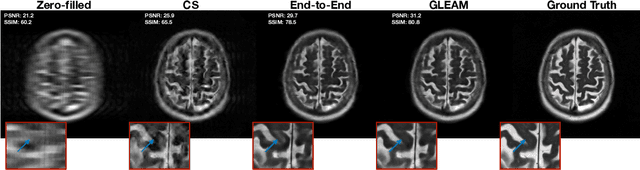

Abstract:Unrolled neural networks have recently achieved state-of-the-art accelerated MRI reconstruction. These networks unroll iterative optimization algorithms by alternating between physics-based consistency and neural-network based regularization. However, they require several iterations of a large neural network to handle high-dimensional imaging tasks such as 3D MRI. This limits traditional training algorithms based on backpropagation due to prohibitively large memory and compute requirements for calculating gradients and storing intermediate activations. To address this challenge, we propose Greedy LEarning for Accelerated MRI (GLEAM) reconstruction, an efficient training strategy for high-dimensional imaging settings. GLEAM splits the end-to-end network into decoupled network modules. Each module is optimized in a greedy manner with decoupled gradient updates, reducing the memory footprint during training. We show that the decoupled gradient updates can be performed in parallel on multiple graphical processing units (GPUs) to further reduce training time. We present experiments with 2D and 3D datasets including multi-coil knee, brain, and dynamic cardiac cine MRI. We observe that: i) GLEAM generalizes as well as state-of-the-art memory-efficient baselines such as gradient checkpointing and invertible networks with the same memory footprint, but with 1.3x faster training; ii) for the same memory footprint, GLEAM yields 1.1dB PSNR gain in 2D and 1.8 dB in 3D over end-to-end baselines.